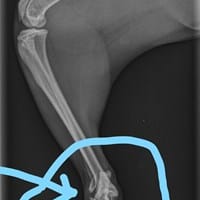

Es fractura o es un esguince?